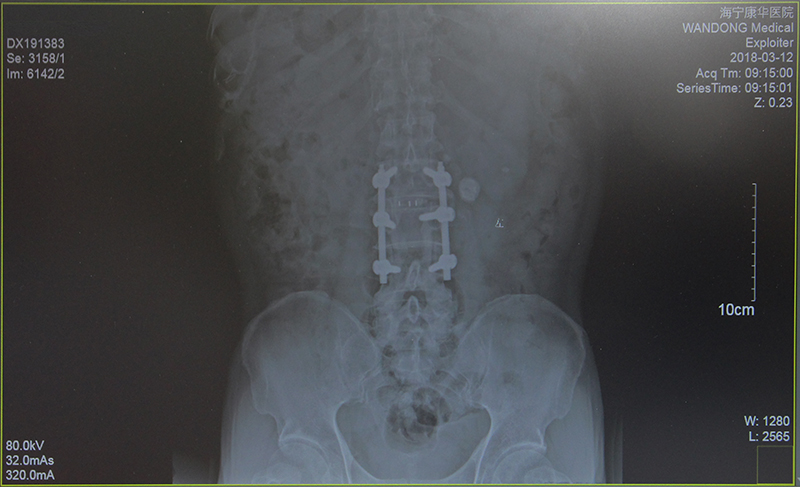

经过详细的术前检查与计划,2月2日,在鲍立峰主刀下,为沈大伯进行了“腰2/3,腰3/4减压术及腰2/3椎体融合术”。整台手术历时约3小时,较好地纠正了大伯多处突出的腰椎。第二天,沈大伯的左下肢已经恢复了肌力。随后,配合康复治疗等,两周后,大伯顺利出院了,此时的他已经基本可以靠着拐杖独立行走了。

(术后)